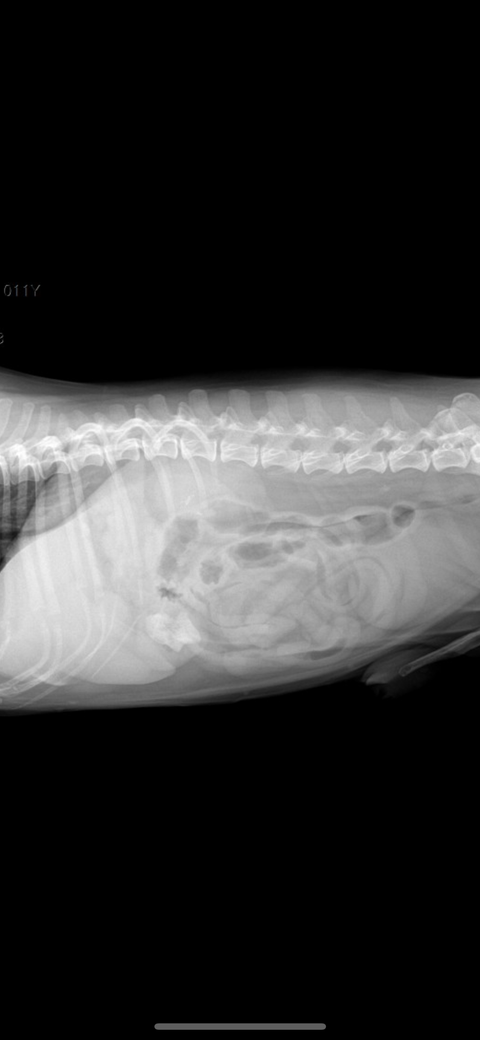

엄마가 2일 전과 1일 전에 시츄에게 족발을 주어서 2일 전부터 간헐적으로 토하다가 금일 새벽에 12번 정도 토를 하고 2cm 정도 되는 뼈를 토했습니다. 그리고 변도 조금씩 묽게 싸고 금일 새벽에 뼈를 포함한 저런 똥을 쌌습니다. 사진에 보시다시피 피가 살짝 섞여있습니다. 그래서 병원을 방문하였더니 위에 뼈가 있는 것이 아니라 소장에 가로 2.7cm 세로 2cm 정도의 뼈가 들어있는 거 같다고 판단하셨습니다. 강아지가 11살이라 나이도 있고 디스크로 인해 스테로이드를 3주 정도 복용하여 간수치가 좋지 않다고 하여 수술을 해야 할지 고민이 된다고 하시고 당장 수술을 결정하자니 뼈가 그리 크지 않아 위에 사진처럼 나올 수도 있을 거 같다 보호자 의견에 따르겠다고 말씀하셨습니다. 수술을 결정하지 않는 판단을 보호자가 하신다면 오늘 5시간 정도 수액을 맞고 엑스레이를 다시 찍어본 후 뼈가 좀 내려갔는지 확인을 해보면서 지켜보는 방향으로 가자고 하셨습니다. 하지만 금일은 금식 금수이지만 내일 밥을 주고 물을 줬을 때 토하게 된다면 병원에 방문하여 수술을 고려하자고 하셨습니다. 수의사 선생님들의 의견을 듣고 싶습니다..

주치의의 판단이 옳은 부분이 많지만, 통상 구토를 12번이나 할정도로 이물 폐색 가능성이 높으면서 방사선 사진에서 폐색부가 저런 양상으로 보인다면 바로 배를 여는게 교과서적인 추천사항입니다.

폐색이 유지되면 이차적인 췌장염과 장괴사가 가능하여 환자를 잃을 수 있으니 방사선 사진을 다시 촬영하시고 이물이 관찰된다면 바로 배를 여는것을 추천합니다.